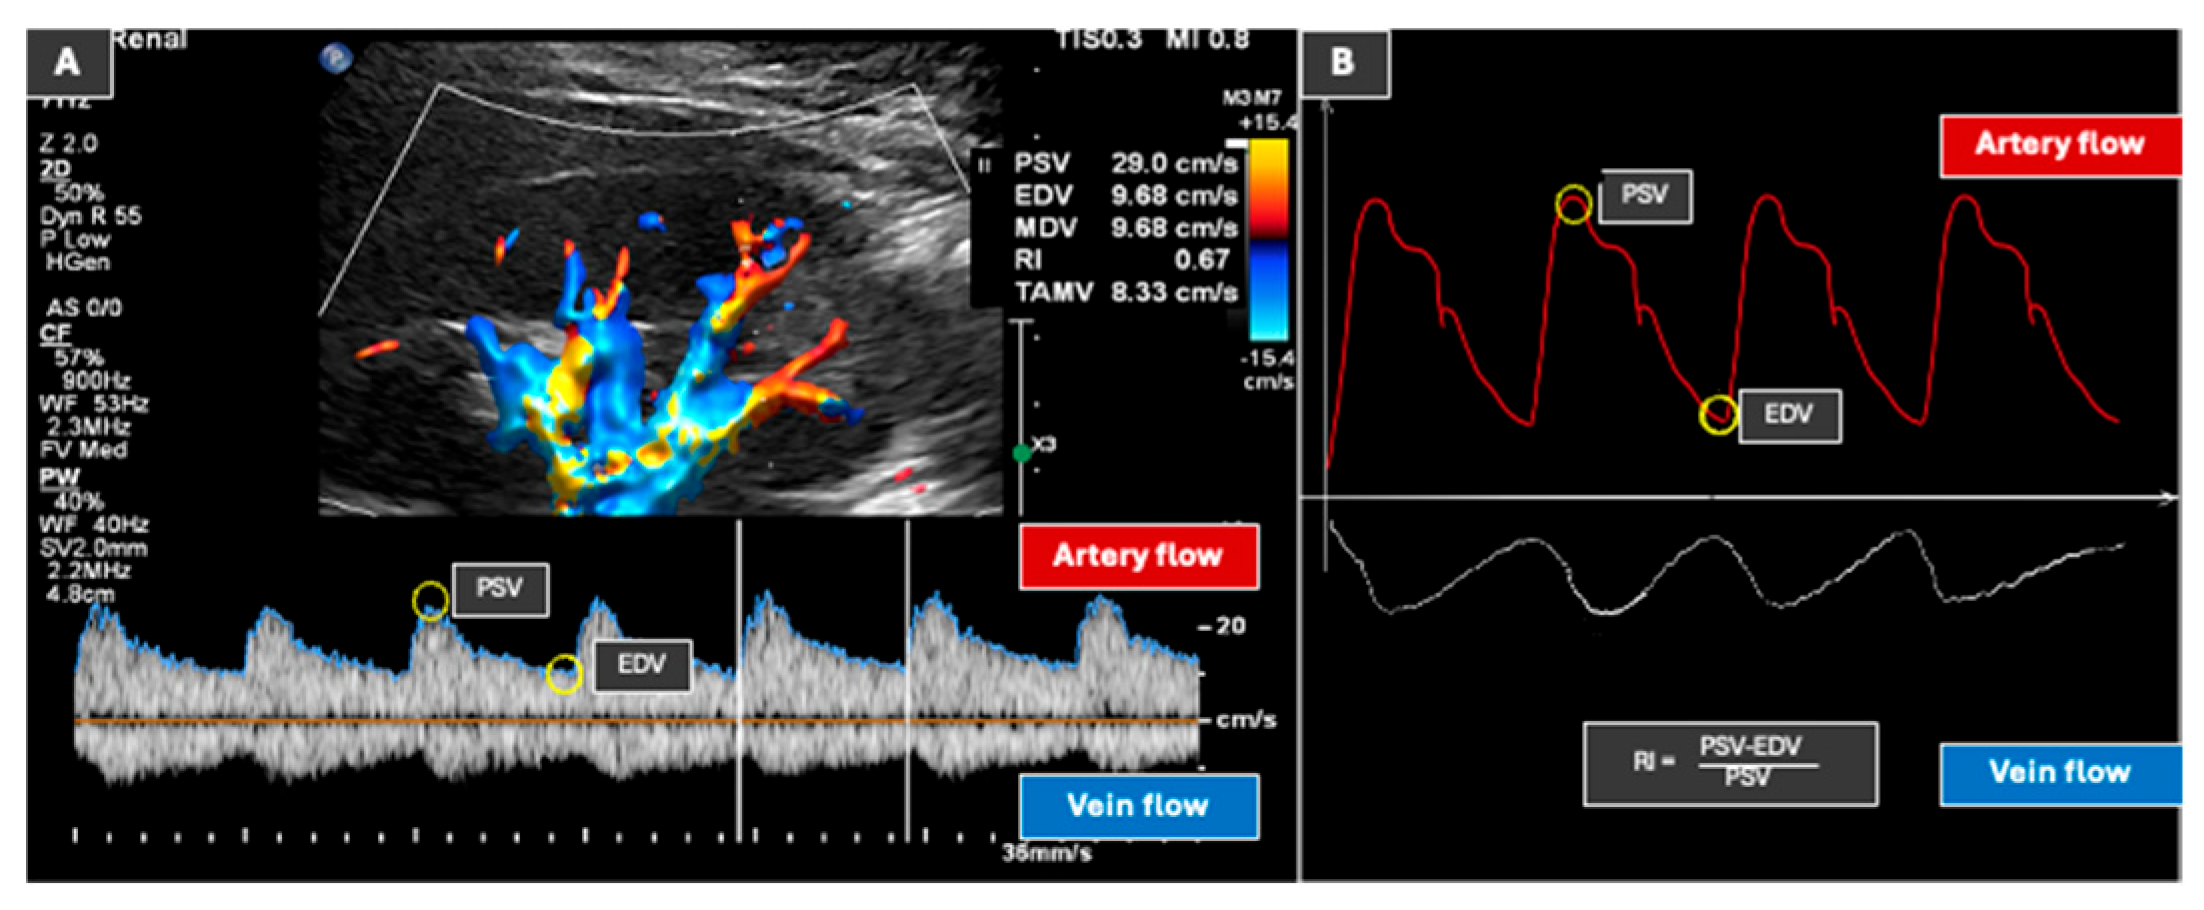

9. Doppler Ultrasound (Vasculature Assessment)